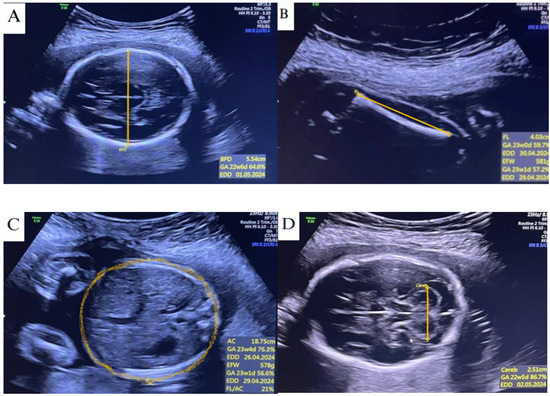

2.2. Ultrasonography

2.3. TCD Measures